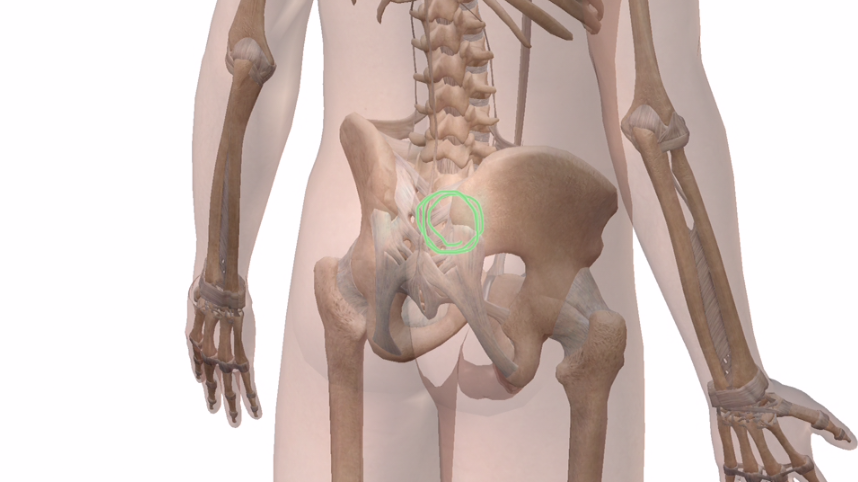

とにかく、ココです↓

体を透かして見るとこんな感じです↓

この骨が出っ張っているところが上後腸骨棘です。

お尻あたりを触るとお尻の割れ目の少し上外側あたりにある出っ張ったところです。

上前腸骨棘ってこちら↓

ここです。

この辺のポコッとしているあたりです。

この緑矢印の方向に押します。

この痛みはおそらく上後腸骨棘ではなく、もう少し中の仙腸関節(骨盤のなかの関節)に痛みが出ているのだと思います。

ここが痛くなる原因は、仙腸関節が良く動いていないからだと思います。

上前腸骨棘から動きの渋くなっている仙腸関節を動かすと、痛みが取れやすいです。

※画像出展:VISIBLE BODY®